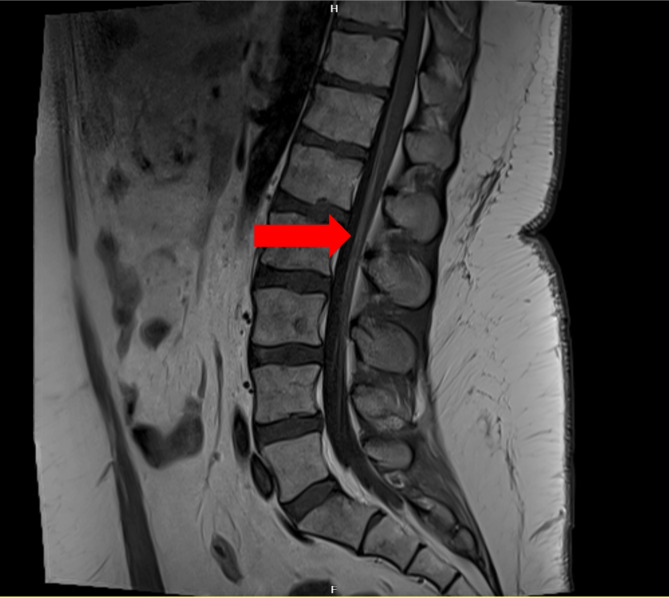

Guillain-Barré syndrome is the most common acute inflammatory demyelinating peripheral nerve condition. Occasionally, other autoimmune conditions can mimic Guillain-Barré syndrome but may require different diagnostic workup and treatment. We report here two patients with Evans syndrome, a rare hematological autoimmune condition who developed a subacute inflammatory radiculopathy. Similarities and distinguishing clinical and diagnostic features are discussed.